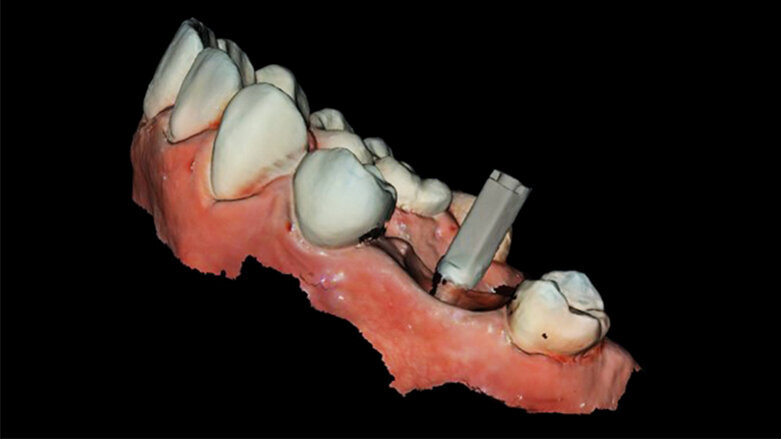

V listopadu roku 2017 se dostavila 39letá pacientka na vstupní vyšetření do White Clinic z důvodu bolesti zubu 16. Bylo provedeno klinické a radiografické vyšetření, včetně periapikálního snímku, CBCT skenu (Carestream 9600, Carestream Dental) a intra a extraorálních fotografií (obr. 1–3).

Při klinickém a radiografickém zhodnocení bylo zjištěno, že u zubu 16 byla přítomna cervikální resorpce v meziobukálním kořeni. Zvolený léčebný plán byl extrakce zubu a okamžité zavedení implantátu. Zub byl již v minulosti endodonticky přeléčen a ošetřen definitivní keramickou korunkou. Přestože je protokolem White Clinic zachovávání zubů, zub byl indikován k okamžité extrakci vzhledem ke stavu v dané situaci. Také z důvodu nedostatku času, nebyl náš digitální tým schopen vyrobit chirurgickou šablonu pro zavedení implantátu, proto zahrnoval léčebný plán chirurgickou fázi a digitální protetickou fázi.